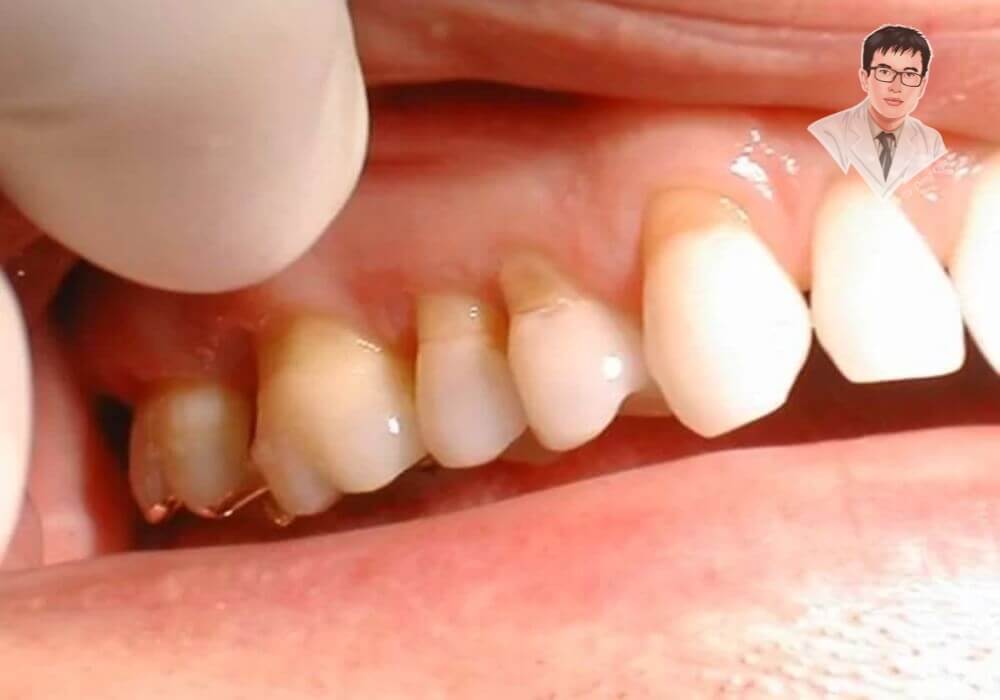

Tụt nướu chân răng là tình trạng mô lợi bao quanh răng dần co lại, khiến chân răng lộ ra ngoài. Điều này làm mất đi sự bảo vệ tự nhiên, dễ gây ê buốt và tạo điều kiện cho vi khuẩn tấn công gây các bệnh lý nha chu. Hình ảnh trước và sau khi tụt lợi sẽ giúp bạn dễ dàng nhận biết rõ hơn vấn đề này, từ đó chủ động bảo vệ sức khỏe răng miệng.

Khi tình trạng tụt nướu chân răng tiến triển, các dấu hiệu sẽ trở nên rõ ràng hơn. Chân răng bị lộ ra ngoài rõ rệt, nướu tụt sâu tạo thành khe hở giữa các răng, dễ mắc thức ăn gây khó chịu và mất thẩm mỹ. Ở giai đoạn muộn, răng có thể lung lay, báo hiệu nguy cơ mất răng nếu không được điều trị kịp thời.

Phương pháp điều trị tụt lợi cơ bản và hiệu quả đầu tiên chính là cạo vôi răng và làm sạch túi nha chu. Thủ thuật này giúp loại bỏ hoàn toàn các mảng bám, vi khuẩn nằm sâu dưới đường viền nướu, giảm viêm lợi chân răng và hỗ trợ phục hồi mô nướu tự nhiên. Đây là bước điều trị ban đầu được các nha sĩ ưu tiên thực hiện.